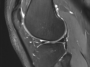

MR cihazları tesla gücüne göre sınıflandırılırlar. İlk MR cihazları 0.02 tesla gücündeydi ve çekimler çok uzun sürüyordu, görüntüler silik görünüyordu. sonra 0.5 ve 1 tesla MR cihazları kullanıma girdi ve süreler biraz kısaldı, görüntüler daha netleşti. Son 30 yılda 1.5 tesla MR cihazları kullanıma girince görüntüler daha netleşti ve çekim süreleri daha da kısaldı. MR Spektroskopi, MR Traktografi, Fonksiyonel MR, Kardiak MR gibi yeni MR çekim teknikleri kullanıma girdi. Son 20 yılda 3 tesla MR cihazları kullanıma girince tüm bu yenilikler ve normal MR çekimlerindeki görüntü kalitesi daha da arttı ve çekim süreleri kısaldı. Hastaların girdiği tüneller genişledi, hasta konforu arttı. 3 teslanın yüksek manyetik alan gücü nedeniyle 1.5 tesla cihazlara göre sekansların süresi kısaldığı gibi kesit kalınlıkları azaldı ve görüntülerdeki netlik arttı. Anatomi çok daha net değerlendirilebilir oldu. Ayrıca MR spektroskopi çok daha küçük alanlardan yapılabilir oldu, diffüzyon çekimlerindeki gelişmelerle Multiparametrik Prostat MR çok daha kaliteli ve ince kesitli görüntülerle çekilmeye başlandı. T1,T2 Mapping Perfüzyon MR çekimleri daha kısa sürelerde ve ince kesitlerle gerçekleştirilebilir oldu.

3 tesla MR cihazının yüksek tesla gücü sayesinde düşük teslalı cihazlara göre daha hızlı, ince kesitli ve kaliteli görüntüleme yapılabilir. Ayrıca Fonksiyonel MR inceleme, Traktografi, Spektroskopi gibi ileri düzey görüntülemelerde fark daha fazladır. Spinal kitlelere spektroskopik inceleme yapılabilir. Yapay zeka sayesinde sekanslar normalden 4 kat daha hızlandırılabilir. Gerektiğinde “Sessiz MR” çekimi ile hastalarımız için daha konforlu ortam sağlanabilir. Tüm vücut MR çekimleri daha hızlı ve kalitelidir. MR çekimi, özellikle klostrofobik hastalar için 70 cm geniş magnet ve televizyon seyretme, müzik dinleme imkanı ile daha konforludur. Kalp MR, Multiparametrik Prostat ve Karaciğer MR gibi özellikli çekimler 3 tesla MR cihazı ile daha kalitelidir. 250 kiloya kadar ağırlığı olan hastalara MR çekimi yapılabilir. Vaskülit için damar görüntüleme, periferik sinirler için MR Nörografi çekimleri yapılabilir